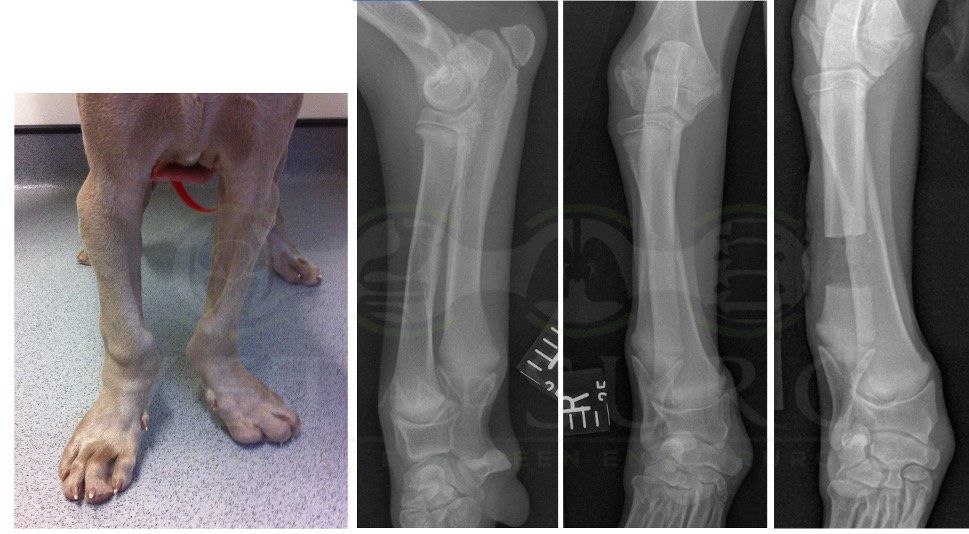

Fracture Salter-Harris sur un chaton Européen de 10 mois

Spike, chaton européen mâle de 10 mois, a été présenté en consultation pour boiterie du membre postérieur droit à la suite d'une chute depuis le 1er étage.

A la radiographie, une fracture de type Salter-harris 1 est diagnostiquée, avec déplacement de l'about discal.